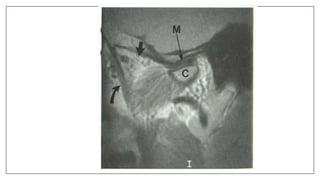

MRI in space infection

• Used in deep neck space infection: Retropharyngeal and Parapharyngeal